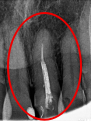

女性Sさん 50代(オールセラミック冠)

主訴

左上の差し歯がとれたままになっている。

治療内容

レントゲンを撮り詳しく診てみると、歯根が破折して保存することができず、抜歯する必要があることがわかりました。抜歯後、オールセラミックブリッジで補綴(欠損した部分を人工物で補う)しました。ブリッジの支台になっている後方の歯は、根尖性歯周炎(根の先端で問題を起こしている)でしたので、根管治療をしています。

所感

抜歯後、欠損部分を補う方法には、1本だけの部分入れ歯、ブリッジ、インプラントの3つの方法があります。この患者さんは、ブリッジを選択されました。メタルフリーの治療を希望されましたので、土台をファイバーコアにし、オールセラミックのブリッジをかぶせました。患者さんは、お口の中の金属を徐々に減らしていきたいということです。体全体の健康のことを考えると正しいことです。

オールセラミック冠(失活歯)1本:¥104,500(税込)

オールセラミック冠(生活歯)1本:¥93,500(税込)

ポンティック1本:¥93,500(税込)

合計:¥291,500(税込)